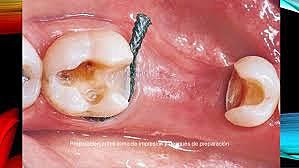

• Preparación para incrustación de las piezas 3.6 y 4.7

Preparación para incrustación de las piezas 3.6 y 4.7

Debido a que la extensión de diente que se tiene que restaurar es amplia se decidió en colocar incrustaciones. Se aísla, y se preparan las paredes de la cavidad de forma convergente. Finalmente se toman modelos y se obtura de forma provisional. El modelo se manda al laboratorio para poder realizar el diseño de la incrustación.